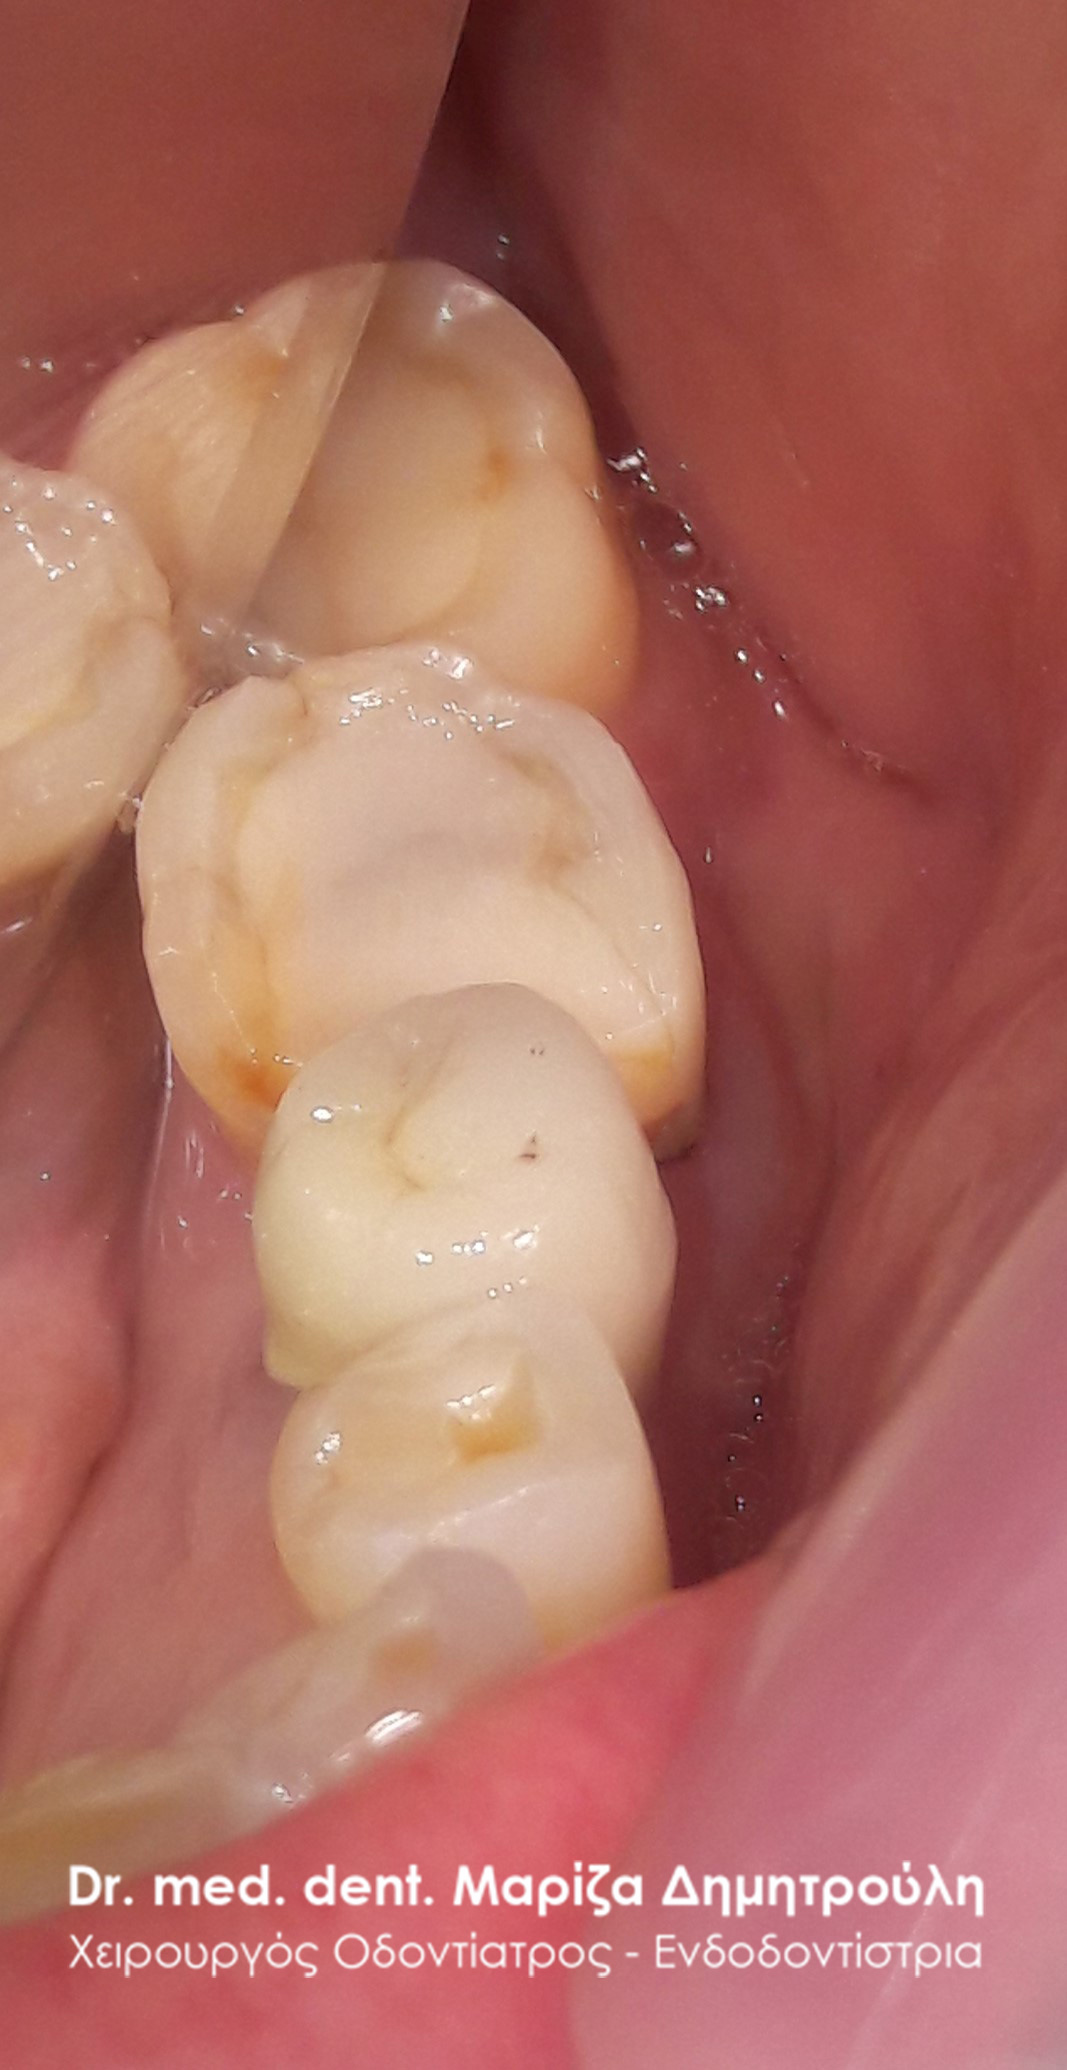

Περιστατικό – Σφραγίσματα δοντιών και θήκη δοντιού

Η ασθενής προσήλθε στο ιατρείο με την επιθυμία να αποκαταστήσει τα δόντια της. Μετά την κλινική εξέταση διαπιστώθηκε στην πάνω αριστερή πλευρά ότι 3 δόντια χρειαζόταν την άμεση οδοντιατρική θεραπεία. Όπως φαίνεται και στις φωτογραφίες στον πρώτο προγόφιο και στο δεύτερο γομφίο υπήρχαν παλιές εμφράξεις ρητίνης (λευκά σφραγίσματα) τα οποία είχαν επανατερηδονιστεί. Μετά τον εκτροχισμο των παλιών σφραγισμάτων, αφαιρέθηκε η τερηδόνα που εντοπιζόταν κάτω από τα σφραγίσματα και τα 2 αυτά δόντια αποκαταστάθηκαν με νέα λευκά σφραγίσματα. Ο πρώτος γομφιος παρουσίαζε ένα εκτεταμένο παλιό σφράγισμα αμαλγάματος και επιπλέον ένα κομμάτι του φυσικού δοντιού είχε σπάσει. Λόγω της εκτεταμένης βλάβης του δοντιού αποφασίστηκε η αποκατάσταση του δοντιού με μία στεφάνη (θήκη) ζιρκονίου.

ΠΡΙΝ

META